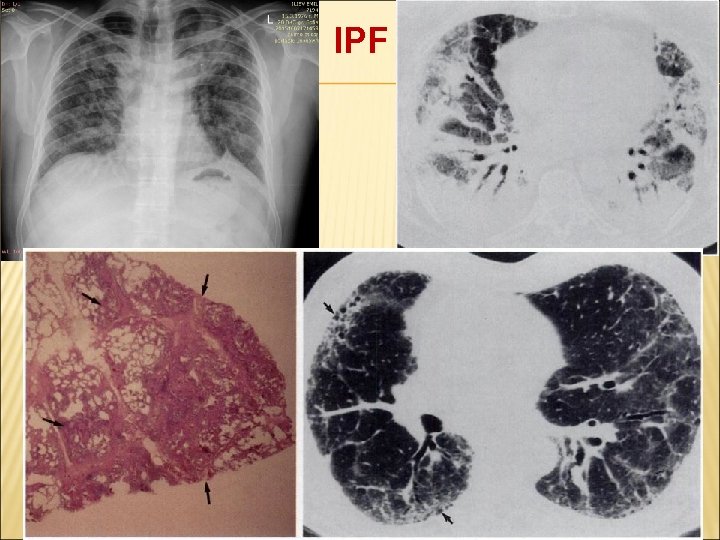

1. ОБИКНОВЕНА ИНТЕРСТИЦИАЛНА ПНЕВМОНИЯ (UIP) ИДИОПАТИЧНА БЕЛОДРОБНА ФИБРОЗА (IPF) КРИПТОГЕНЕН ФИБРОЗИРАЩ АЛВЕОЛИТ (CFA) Образни методи за диагноза – характерни са периферни и базални ретикулeрни сенки, промени тип “пчелна пита”, а в динамика се явяват нови зони на засенчвания тип „матово

ОБИКНОВЕНА ИНТЕРСТИЦИАЛНА ПНЕВМОНИЯ (UIP) ИДИОПАТИЧНА БЕЛОДРОБНА ФИБРОЗА/КРИПТОГЕНЕН ФИБРОЗИРАЩ АЛВЕОЛИТ (IPF/CFA) HRCT: B. Периферни и базални ретикуларни промени, тракционни бронхиектазии. C. Типични промени тип “пчелна пита”. Хистология: ОБИКНОВЕНА ИНТЕРСТИЦИАЛНА ПНЕВМОНИЯ (UIP) 1. Гъста фиброза с ремоделиране на белодробната архитектоника тип”пчелна пита”. 2. Фибробластни фокуси, пръснати предимно субплеврално и парасептално

IPF